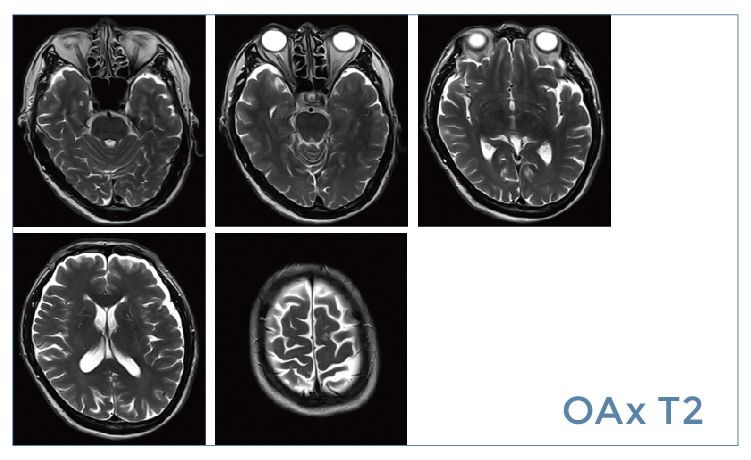

【朗润影像档案】20190531磁共振影像病例结果讨论

【朗润影像档案】磁共振影像病例分享(编号20190531)